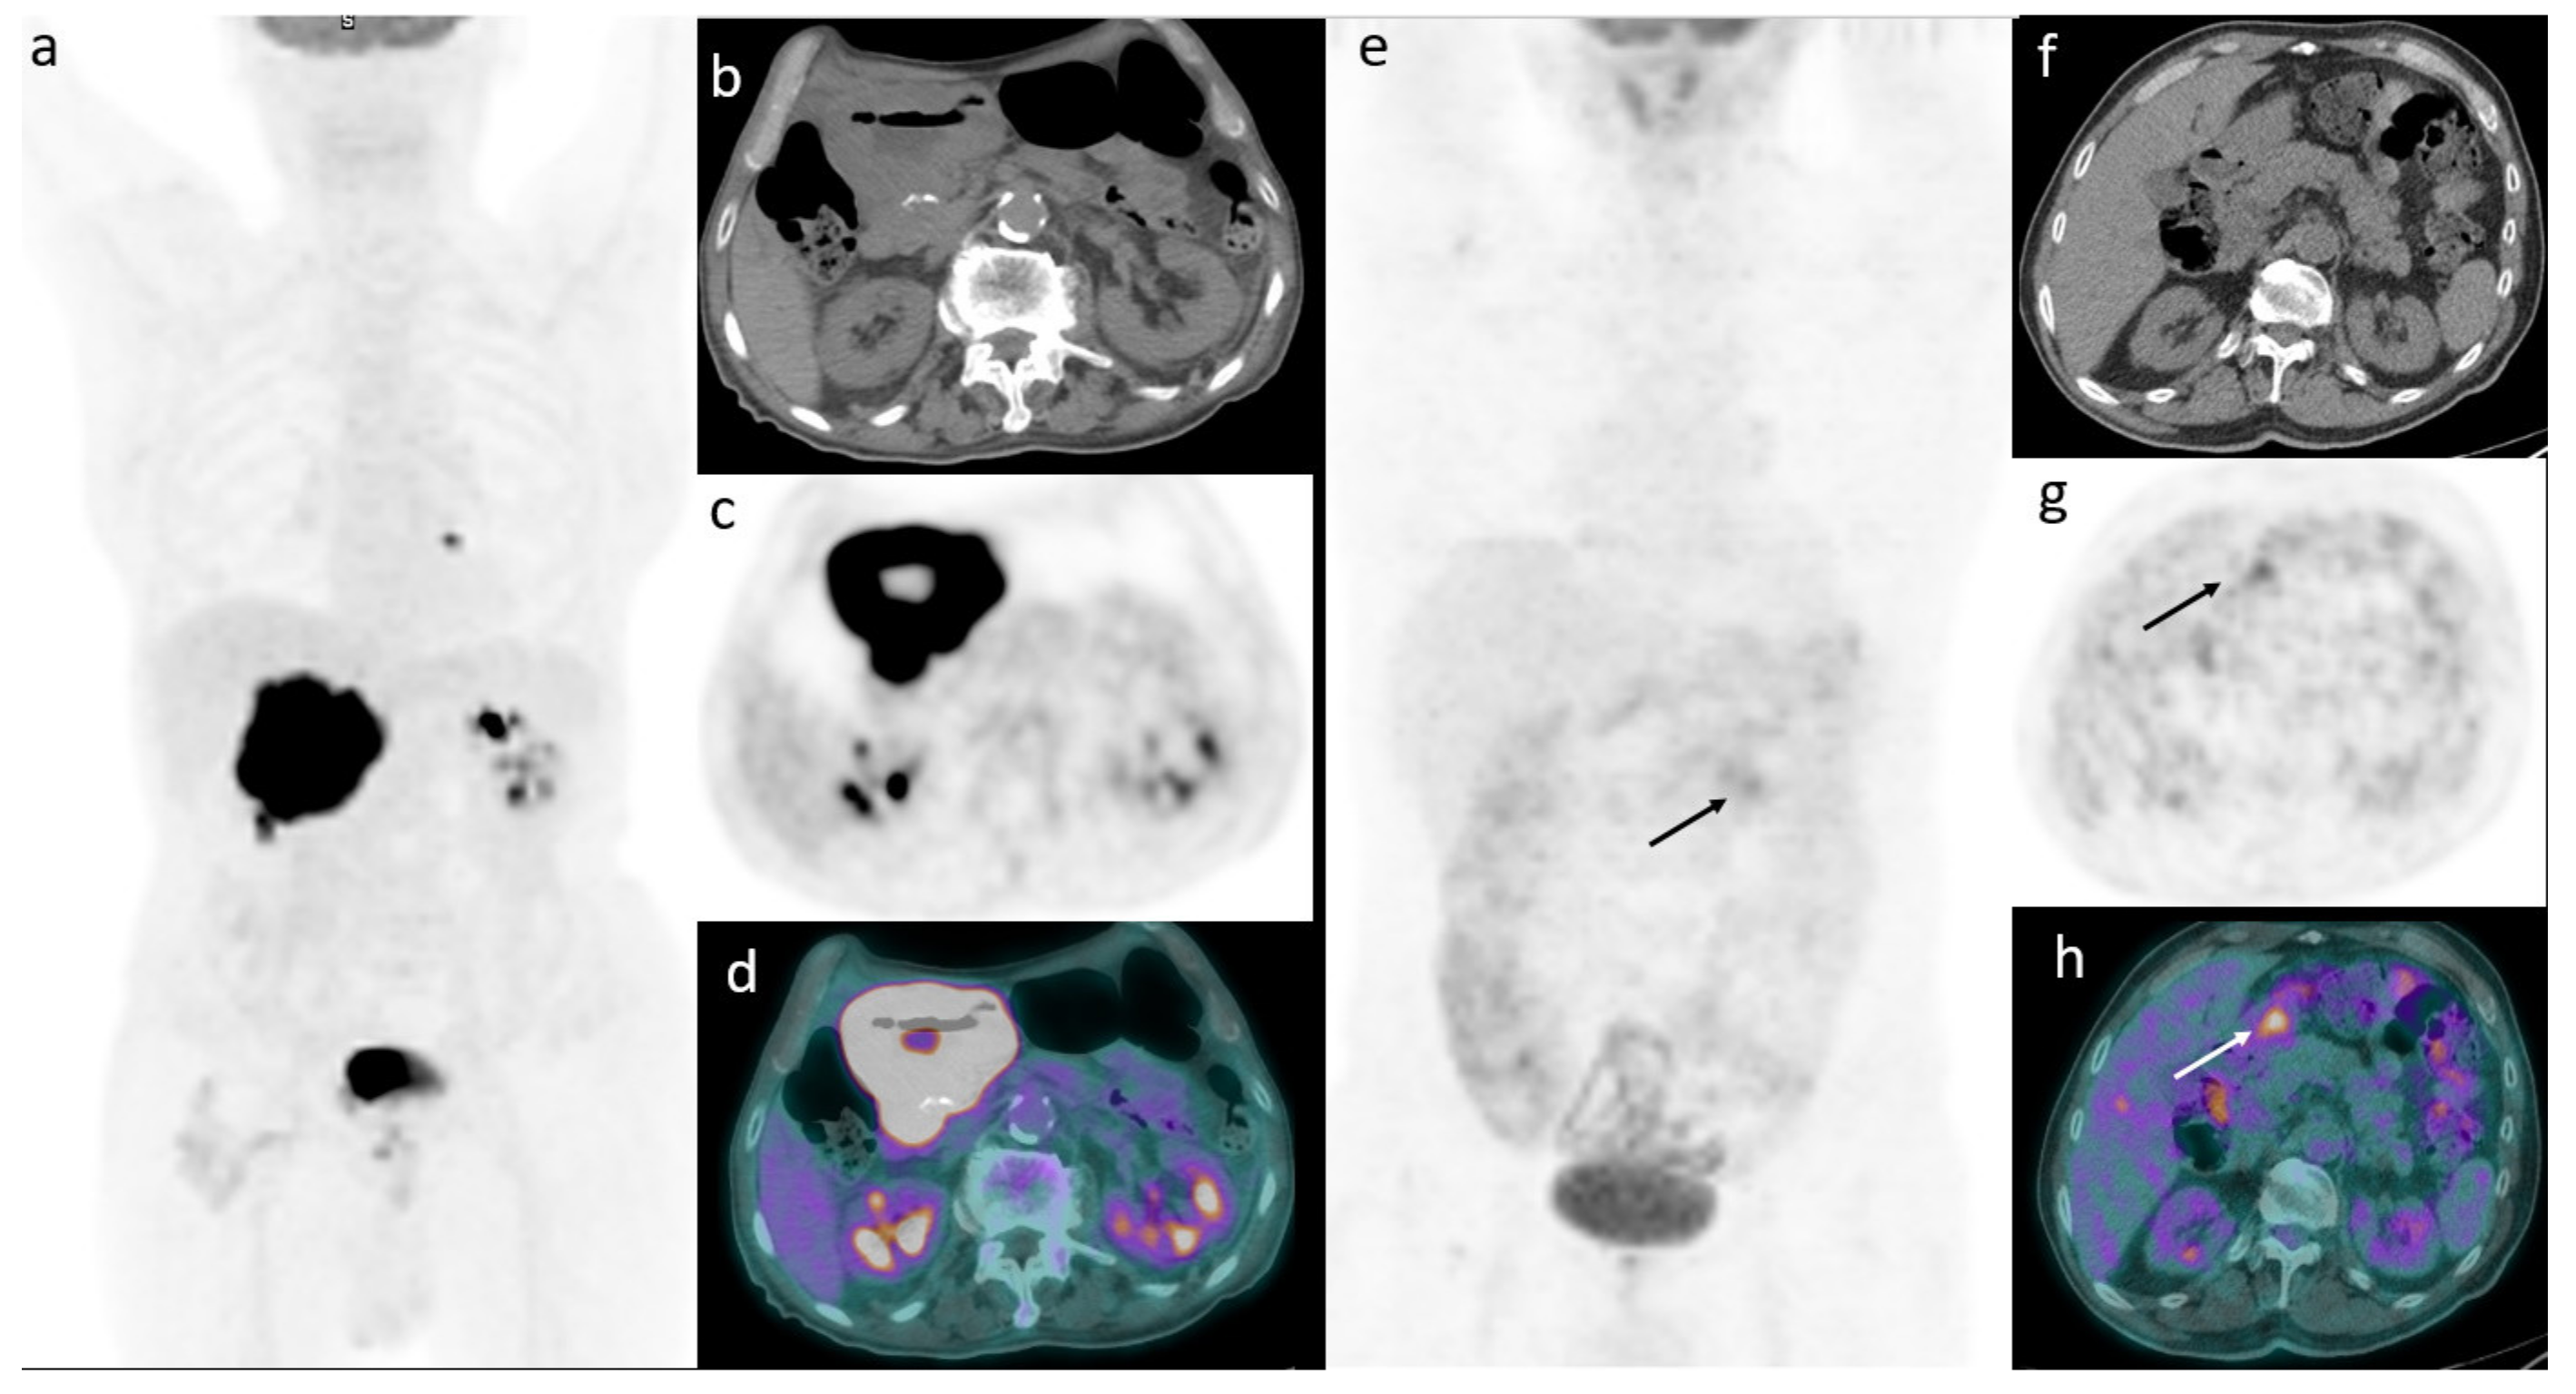

3. Results

3.3. Prognostic Role of 2-[18F]-FDG-PET/CT